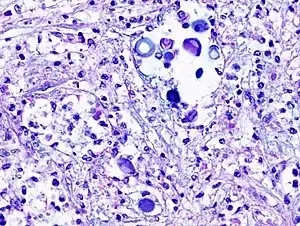

Biopsy

A special stain may be needed to see the cryptococcus capsule.[34]

Mucicarmine stain: bright pink cryptococcosis capsule[34] -

Field stain: thick cryptococcosis capsule -

H&E stain: histiocytic penumonia -